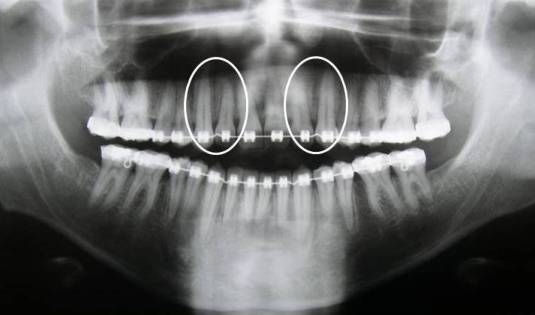

Quando a segmentação da maxila esta prevista no planejamento cirúrgico, solicitamos ao ortodontista a divergência das raízes dos incisivos laterais e caninos superiores, para que a osteotomia possa ser realizada entre as raízes desses dentes com maior segurança.

Em muitas situações de mordida aberta anterior esquelética, solicitamos também que os dentes superiores sejam alinhados e nivelados com o arco ortodôntico segmentado entre incisivos laterais e caninos superiores, para evitar a extrusão dos incisivos, desta forma, a cirurgia segmentada da maxila promoverá o fechamento da mordida aberta esquelética com origem na maxila.